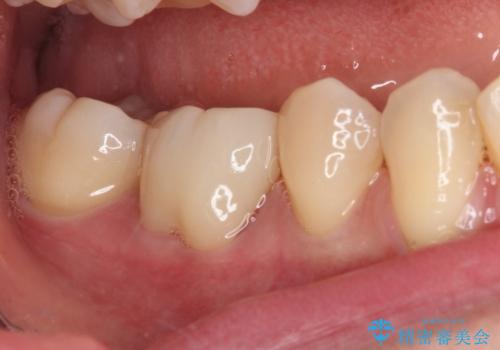

速やかに処置を進めたことで症状は落ち着き、治療後しばらくの状態では神経を取り除く可能性は低くなりました。